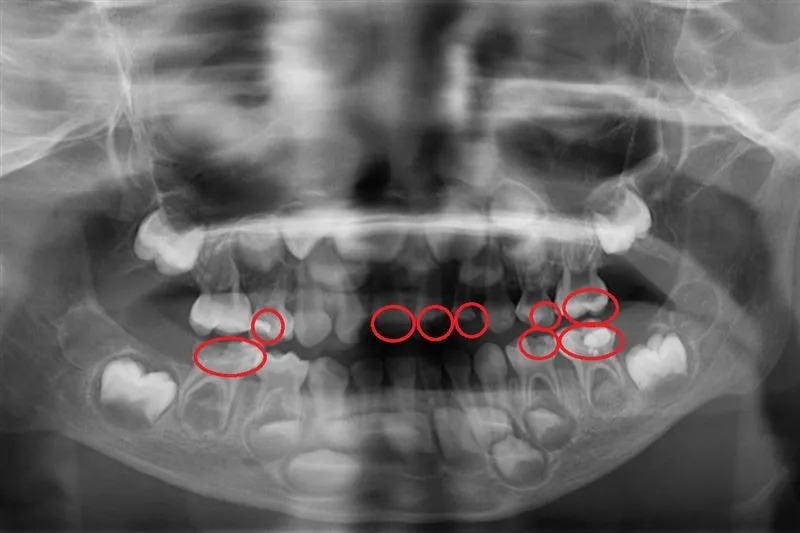

▲孩童蛀牙照(圖/台北慈濟醫院提供)

5 歲小宏在幼兒園定期接受塗氟和口腔檢查,均未察覺異狀,但日前直到卻出現牙痛情形,而且臉頰腫脹相當不舒服,因此被父母帶至就醫。台北慈濟醫院兒童牙科陳默醫師檢查發現,小宏罹患嚴重齲齒並已引發蜂窩性組織炎,雖然積極治療,但最後不得不拔除 4 顆已無法補救的乳牙。陳默醫師對此表示,學校塗氟雖有幫助,但無法取代完整的牙科檢查與X光診斷,家長應該自孩子長牙後就要定期帶至牙科門診檢查,勿等蛀牙惡化才就醫。